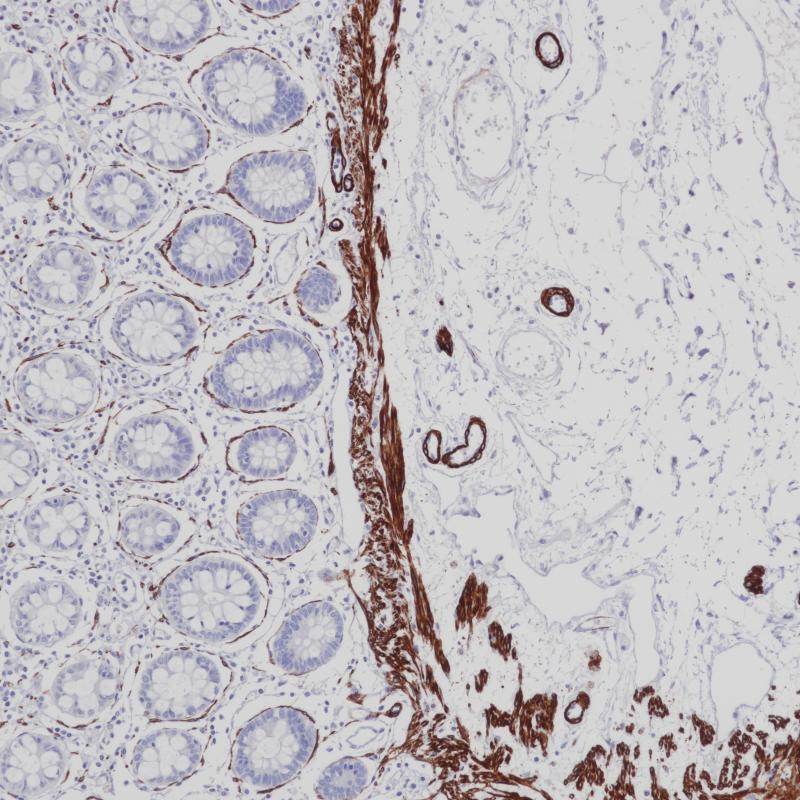

AR-V7 重组兔单克隆抗体

AR V7属于核激素受体家族。它含有核受体DNA结合域。类固醇激素受体是配体激活的转录因子,调节真核基因的表达,影响细胞增殖和分化的目标组织。转录因子的活性受结合共激活因子和共抑制因子的调节。该靶点是雄激素受体的剪接变体,缺乏c端雄激素结合位点。AR-V7在前列腺癌的发生、发展和耐药性的产生中具有重要意义。

阳性对照

前列腺癌

亚细胞定位

细胞核